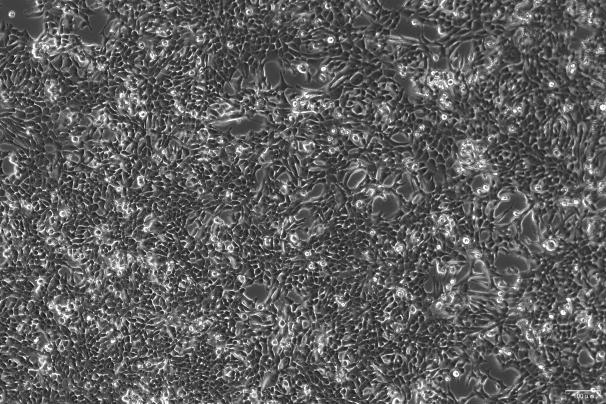

| 细胞特性 | 贴壁生长;上皮细胞样 |

| 培养基 | RPMI-1640+20%FBS +0.01mg/mL Insulin |

| 倍增时间 | 48~72 h |